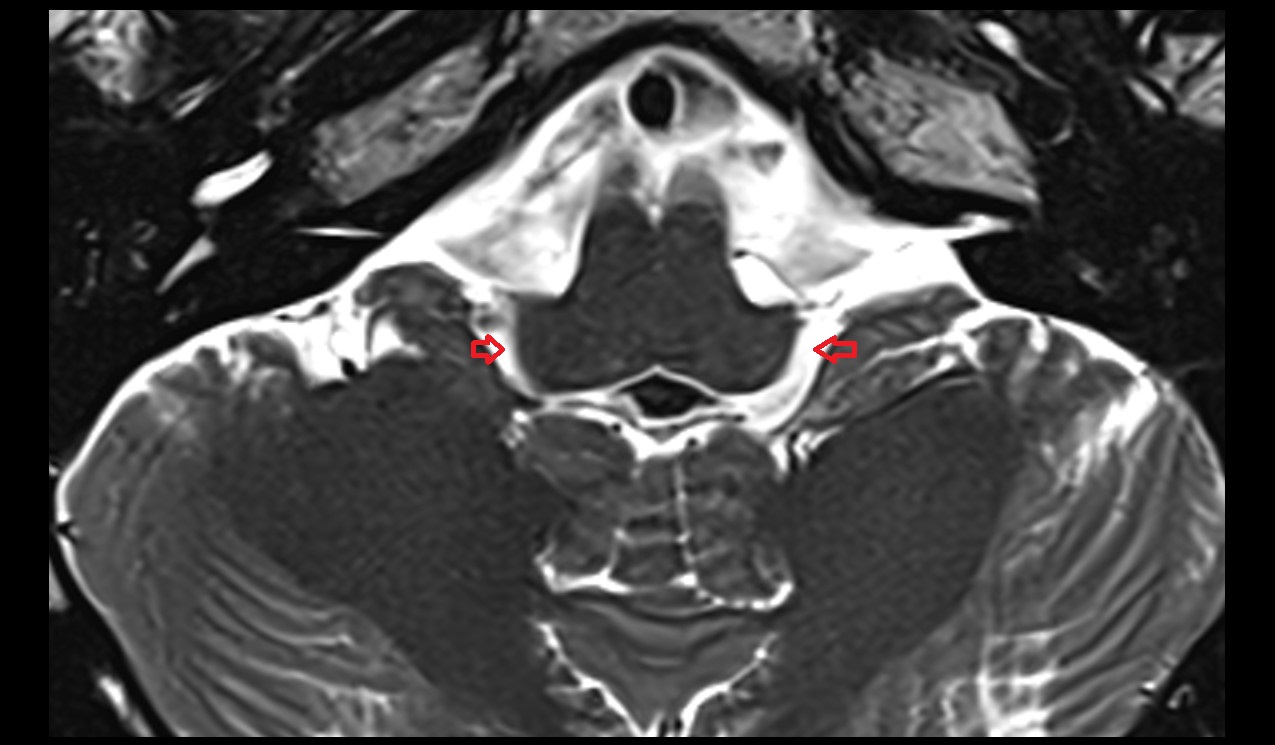

- Lateral aperture of fourth ventricle (foramen of Luschka)